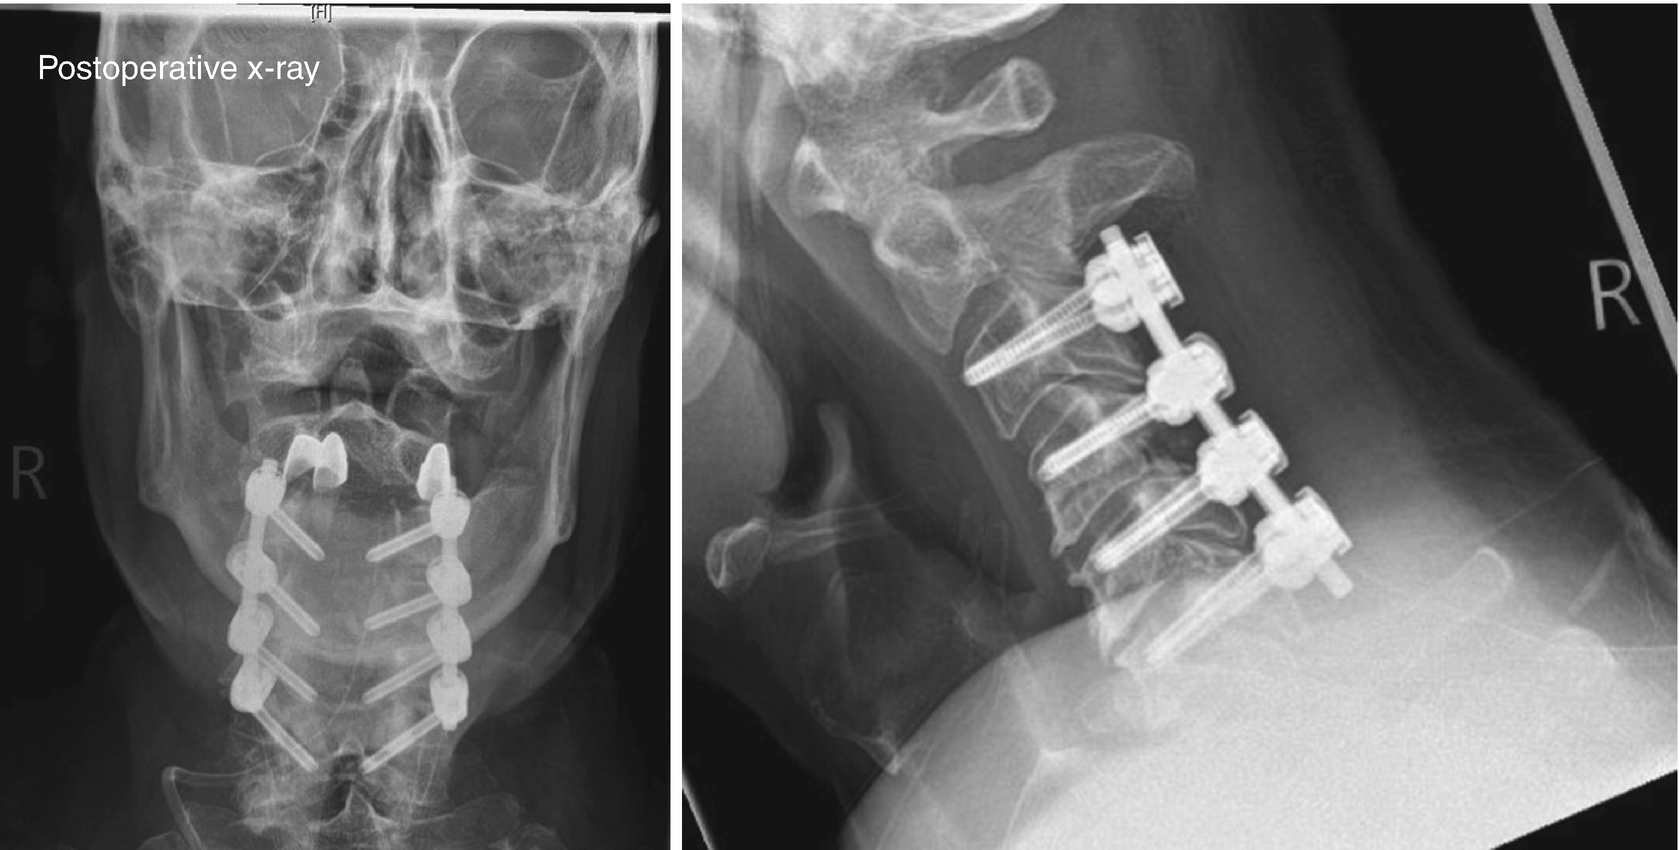

From www.drdilipkiyawat.com

lateral mass fixation done in OPLL. Opll Surgery Risks various methods via anterior or posterior approach with or without. this review focuses on how to maximize benefits, limit risks, and avoid. There were 39 (29.8%) surgical complications in the cohort, which included c5 palsy (7.6%), dural tear (3.1%), surgical. complications associated with surgical management of opll are also discussed. ossification of the posterior longitudinal ligament. Opll Surgery Risks.